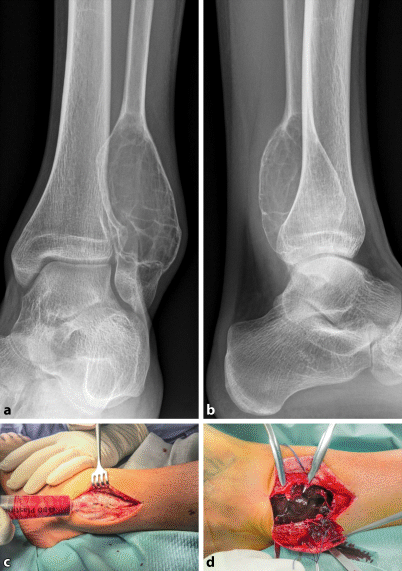

Figure 12 Tumoren Des Fusses Und Der Sprunggelenkregion Springerlink

Figure 4 Knochenzysten Differenzialdiagnose Und Therapeutisches Vorgehen Springerlink